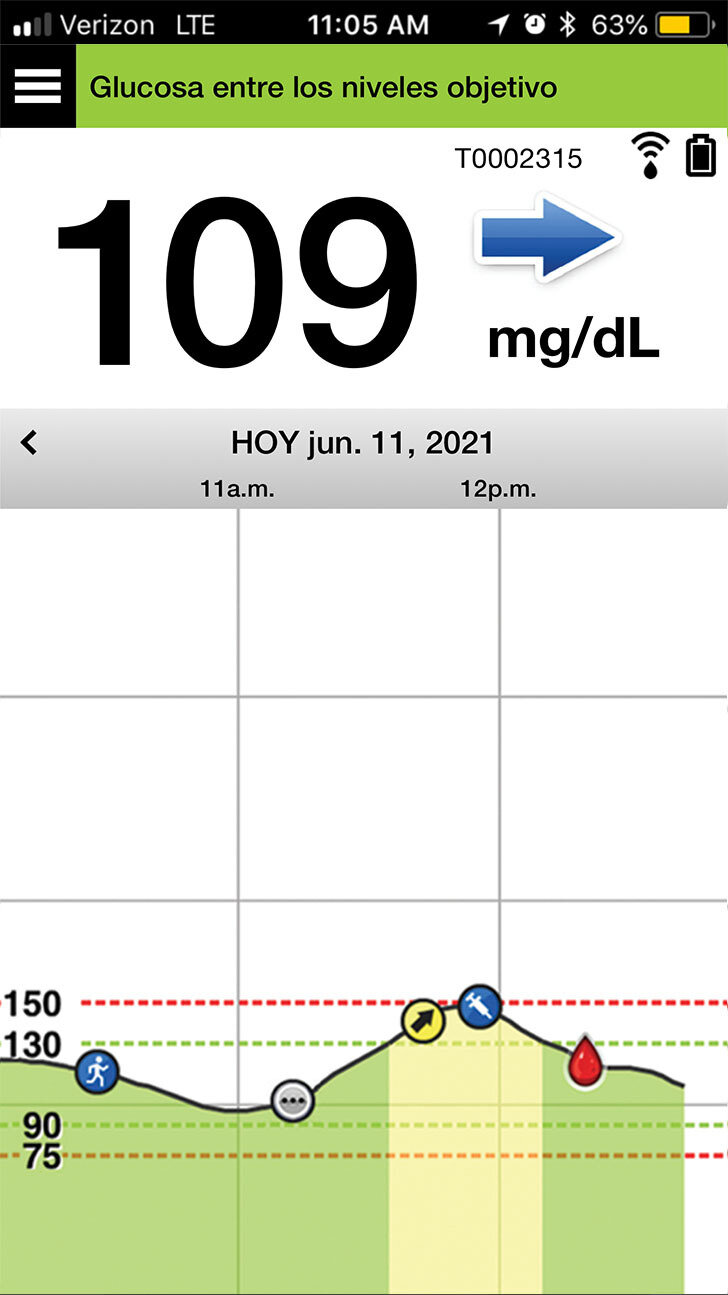

Cuando abre la aplicación para móvil Eversense®,

se muestran principalmente su nivel

de glucosa actual y una flecha de tendencia.

En la parte superior derecha, puede ver

la intensidad de la conexión entre el transmisor y el sensor, y la carga de la batería que tiene

el transmisor.

Y, en la parte inferior, se encuentra el gráfico de tendencia de la glucosa.

Las líneas discontinuas rojas indican los niveles de alerta de glucosa alta y baja, y las líneas discontinuas verdes indican el intervalo objetivo.

Todos los eventos que introduzca en la aplicación (como una calibración, comida, ejercicio

o insulina) o las alertas que reciba, se mostrarán en el gráfico de tendencia con un icono.